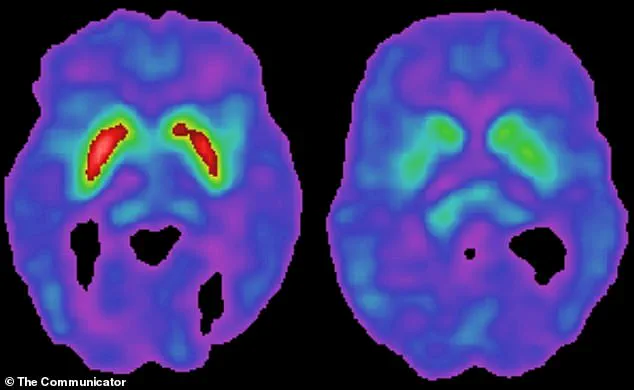

Parkinson’s disease is characterized by the gradual degeneration of dopamine-producing neurons in the brain, leading to symptoms such as tremors, stiffness, and difficulty walking.

The brain’s substantia nigra, a region responsible for producing dopamine, is especially vulnerable to this immune-driven inflammation.

Dopamine is essential for controlling movement, and its depletion leads to the hallmark symptoms of Parkinson’s: stiffness, tremors, and difficulty initiating movement.

The study found that patients with the virus present in their brain tissue exhibited significantly higher levels of toxic tau protein and abnormal levels of key brain proteins.

These findings suggest that the virus may contribute to more widespread brain damage beyond the loss of dopamine-producing neurons, potentially accelerating disease progression.